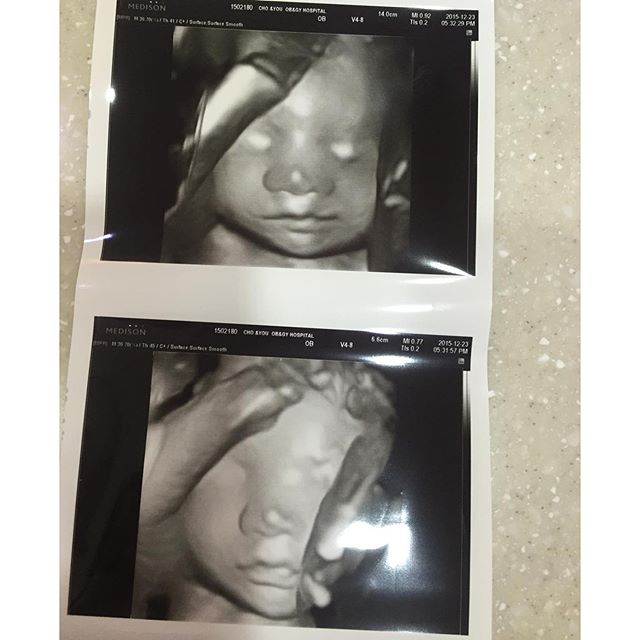

24주 :: 입체초음파 & 임당 검사 & 빈혈 검사 + 임산부 문화생활 (이문세콘서트)

:: 24주 3일 24주 산모 증상 쥐는 안 나지만 무릎 통증 ㅠㅠ 옆으로 누워있을 때 바닥 쪽에 있는 무릎...